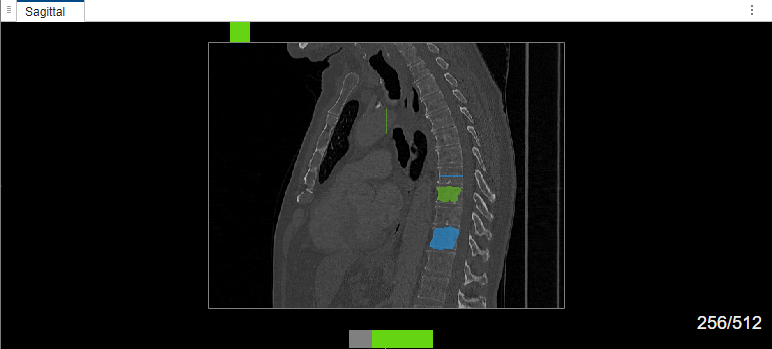

Select label Type1. Draw a bounding box around the object to segment in the sagittal plane of the volume. The MedSAM algorithm extracts the embeddings of the image and segments the object in the bounding box. Then, select label Type2. Draw a bounding box around the object to segment in the sagittal plane of the volume. Because this is the second object segmented in the same image during the same labeling session, the MedSAM algorithm does not extracts the embeddings of the image again. The algorithm directly segments the object in the bounding box.